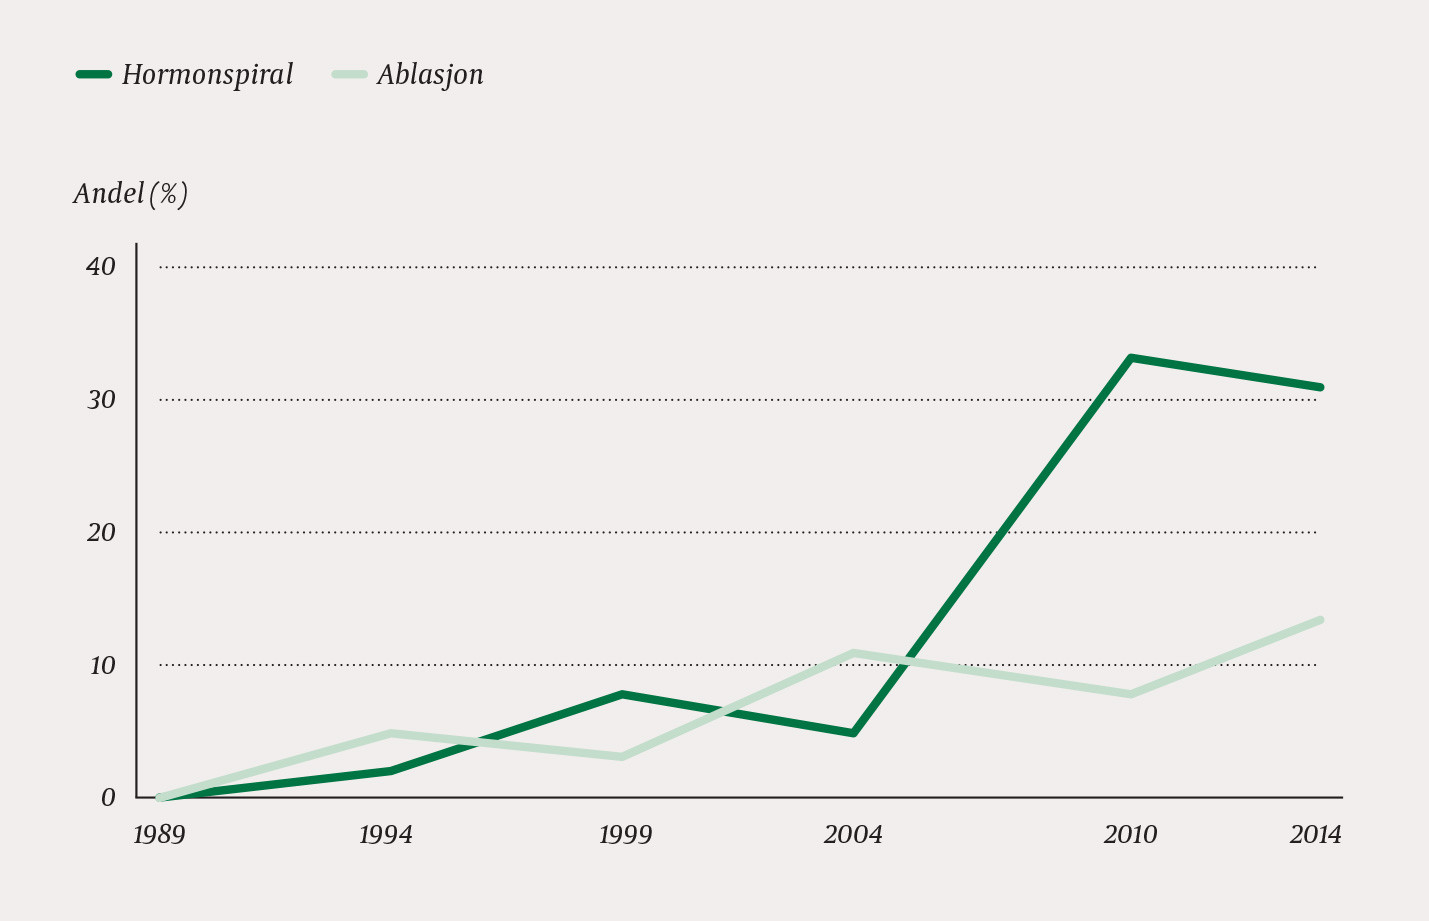

From 1989 to 2014, preoperative diagnosis by dilation and curettage was reduced from 68 % to 4 %, whereas the Pipelle method increased from 8 % to 68 %. In 2014, ultrasound examination was performed in 97 % of patients. While hysterectomies performed with laparotomy fell from 107 in 1989 to 37 per 100 000 women in 2014, vaginal and laparoscopic hysterectomies together increased in the same period from three to 81 per 100 000 women. In 2014, almost half of hysterectomies were performed with robot-assisted laparoscopy. In parallel with the transition from laparotomy to less invasive methods, less bleeding was recorded as well as shorter periods of hospitalization and sickness absence.

Et økende antall kvinner gjennomgikk alternative behandlingsforsøk med endometrieablasjon og/eller hormonspiral før hysterektomi (fig 2). Vi fant økende bruk av bildediagnostikk med CT, MR eller vaginal ultralyd i utredningen. I 2014 ble alle pasientene utredet med bildediagnostikk, de fleste med ultralyd, mot kun 25 % i 1989 (fig 3). Bruk av pipelle for prøvetaking av endometriet har gradvis avløst abrasio, som nå stort sett kun brukes når enkel endometriediagnostikk ikke kan gjennomføres (fig 3).